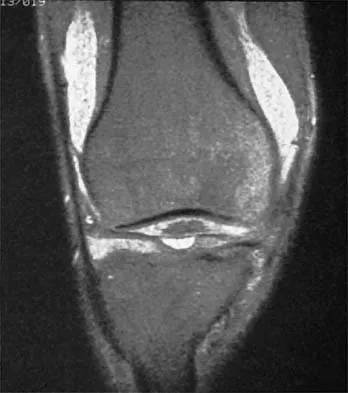

A 30-year-old man who participates in recreational sports reports the spontaneous onset of intermittent pain and swelling about the right knee. Examination reveals a 3+ effusion, with a range of motion of 10 degrees to 60 degrees. He has mild diffuse tenderness but no instability. MRI scans and an arthroscopic view are shown in Figures 39a through 39c. Management should consist of

Explanation